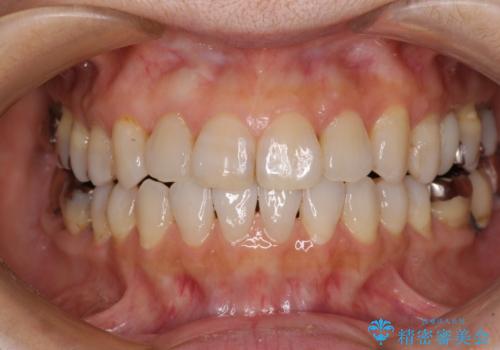

前歯の突出感と上下の隙間 インビザラインによる矯正治療

- 前歯の上下スペースと前歯の隙間を気にして来院された患者様です。

インビザラインにより上下の前歯の隙間を閉じながら、IPRを用いて口元の突出感を合わせて改善していくこととしました。

上下の隙間に舌が入り込むことが、すきっ歯やオープンバイトの原因であったため、舌の筋肉のトレーニングも並行して行い、後戻りの抑制を図りました。